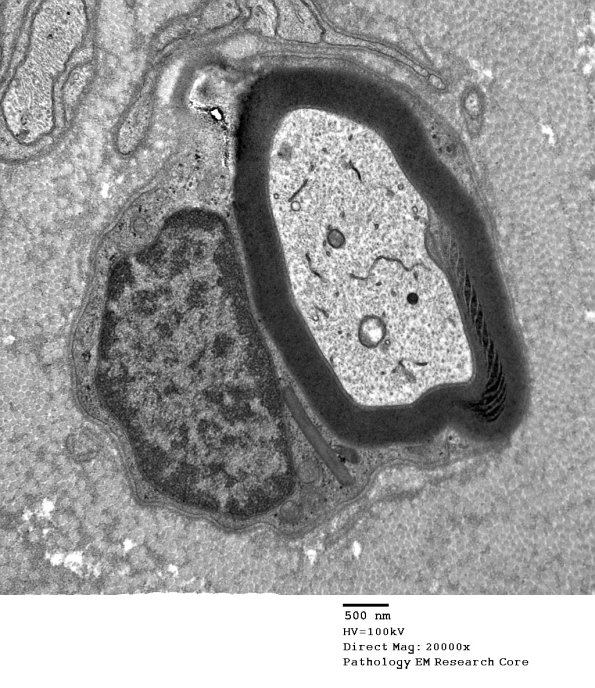

7A1-4 SLC are not always symmetrical. (Electron micrographs)